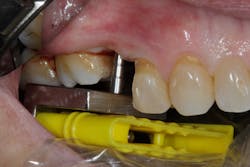

Although restorative and laboratory correction is possible, the best method continues to be prevention—i.e., placing the dental implant in the proper position at the time of surgery.3 Many clinicians still use freehand placement for single- and multiple-unit implant placement, and even with guided surgery, care must be taken when using information from perioperative radiographs to guide the surgical procedure. When taking guide pin radiographs during implant surgery, if the x-ray tube is not perpendicular to the radiographic film/sensor and the depth gauge, distortion of the image may occur (figure 1). This is especially important in a patient with limited opening and at the corners of the mouth in the canine area as there is a higher potential in these areas for alignment error.

The Sniper X-Ray System is a simple device designed to ensure orthogonal x-ray beam alignment and correct osteotomy guide pin positioning so as not to provide false information to the implant surgeon during implant placement (figure 2).